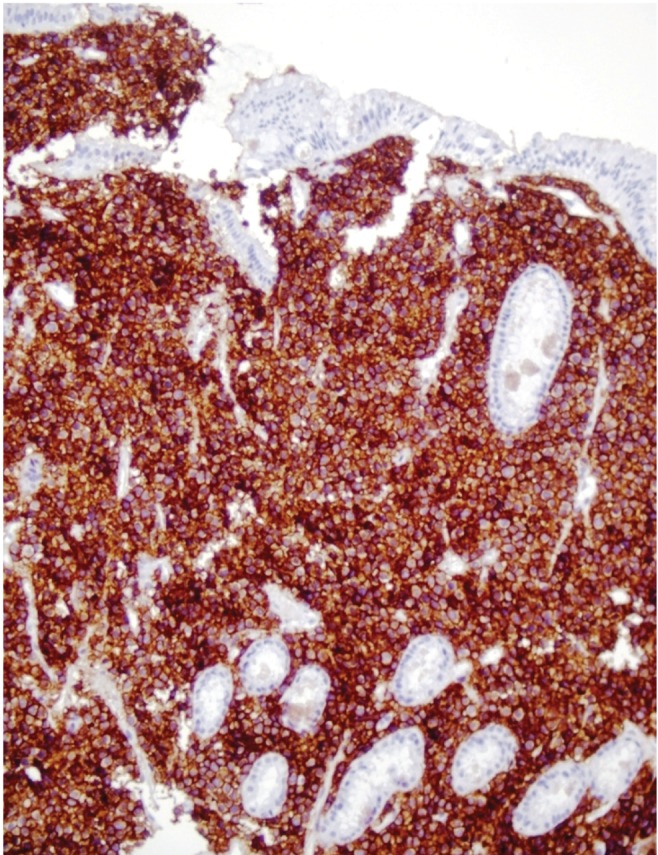

Figure 2

Gastric mucosa with diffuse atypical plasma cell infiltration (H&E, ×40).